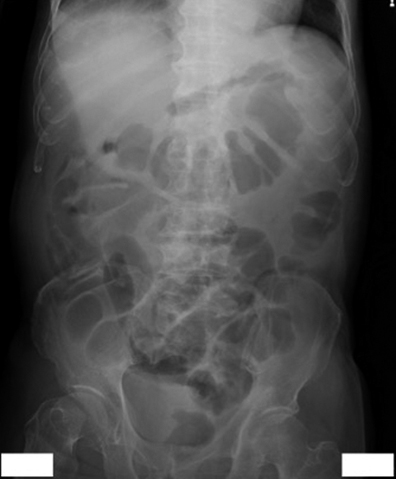

現病歴①:2016年10月,腹痛・下痢精査の下部消化管内視鏡検査(以下,CFSと略記)で全周性の横行結腸癌と診断され自己拡張型金属ステントを留置,上部消化管内視鏡では胃角後壁にIIa+IIc病変を認め胃癌と診断された.2017年1月に手術目的に入院,第4病日に横行結腸切除+幽門側胃切除術を施行した.病理組織所見は大腸癌(T,circ,type 5,40×35 mm,tub2,pT4a,int,INFb,ly0,v2,PN1a,pN0,pPM0(75 mm),pDM0(80 mm),pT4aN0M0,pStage II)および胃癌(M,Post,Type 0-IIc,17×9 mm,tub1,pT1a,ly0,v0,pN0,pPM0(27 mm),pDM0(65 mm),pT1aN0M0,pStage IA)であった.第17病日にドレーン造影で残胃十二指腸吻合の縫合不全を認め(Fig. 1),ドレーン排液の培養よりSerratia marcescensを検出した.第27病日に38.0°Cの発熱を認め,Serratia感染と中心静脈カテーテル感染を念頭にceftriaxone(以下,CTRXと略記)およびVCM点滴を開始した.第36病日に38.2°Cの発熱に加えて腹部膨満,右季肋部痛が出現した.第39病日の血液検査ではWBC 49,620/μl,CRP 19.9 mg/dlの高度炎症反応亢進とBUN 23.6 mg/dl,Cre 1.01 mg/dlの軽度腎機能障害を認め(Table 1),腹部単純レントゲンでは右側結腸の拡張と回腸の一部にもガス貯留を認めた(Fig. 2).腹部超音波検査では胆囊腫大や壁肥厚を認めず,胆囊炎は否定的であった.縫合不全からの敗血症と診断し,CTRXを増量した.炎症反応の改善を認めたためCTRXが有効と判断し,第42病日にVCMを中止したが,第43病日にAST 690 U/l,ALT 471 U/lの肝機能障害が出現した.CTRXによる肝障害を疑い,抗生剤をcefozopranに変更した.その後肝機能障害は徐々に改善し排便は認められたが,37°C台の稽留熱と軽度の腹部膨満は継続した.下痢は認めなかった.第46病日に38~39°Cの弛張熱を認め,腹部骨盤造影CTで全結腸および直腸の壁肥厚像を認め(Fig. 3a~f)腸炎と診断した.第47病日のCFSで直腸からS状結腸にかけてびまん性に偽膜の付着を認め偽膜性腸炎と診断し(Fig. 4),同日の血液検査でAlb 2.1 g/dl,WBC 13,750/μl,臍部に圧痛を認めたが腹膜刺激症状は認めないため,American College of Gastroenterology(以下,ACGと略記)ガイドラインの重症(severe disease)と診断し,VCM 125 mg×4回/日を開始した.

Abdominal X-ray picture demonstrated intestinal gas mainly in the right-sided colon and ileum.